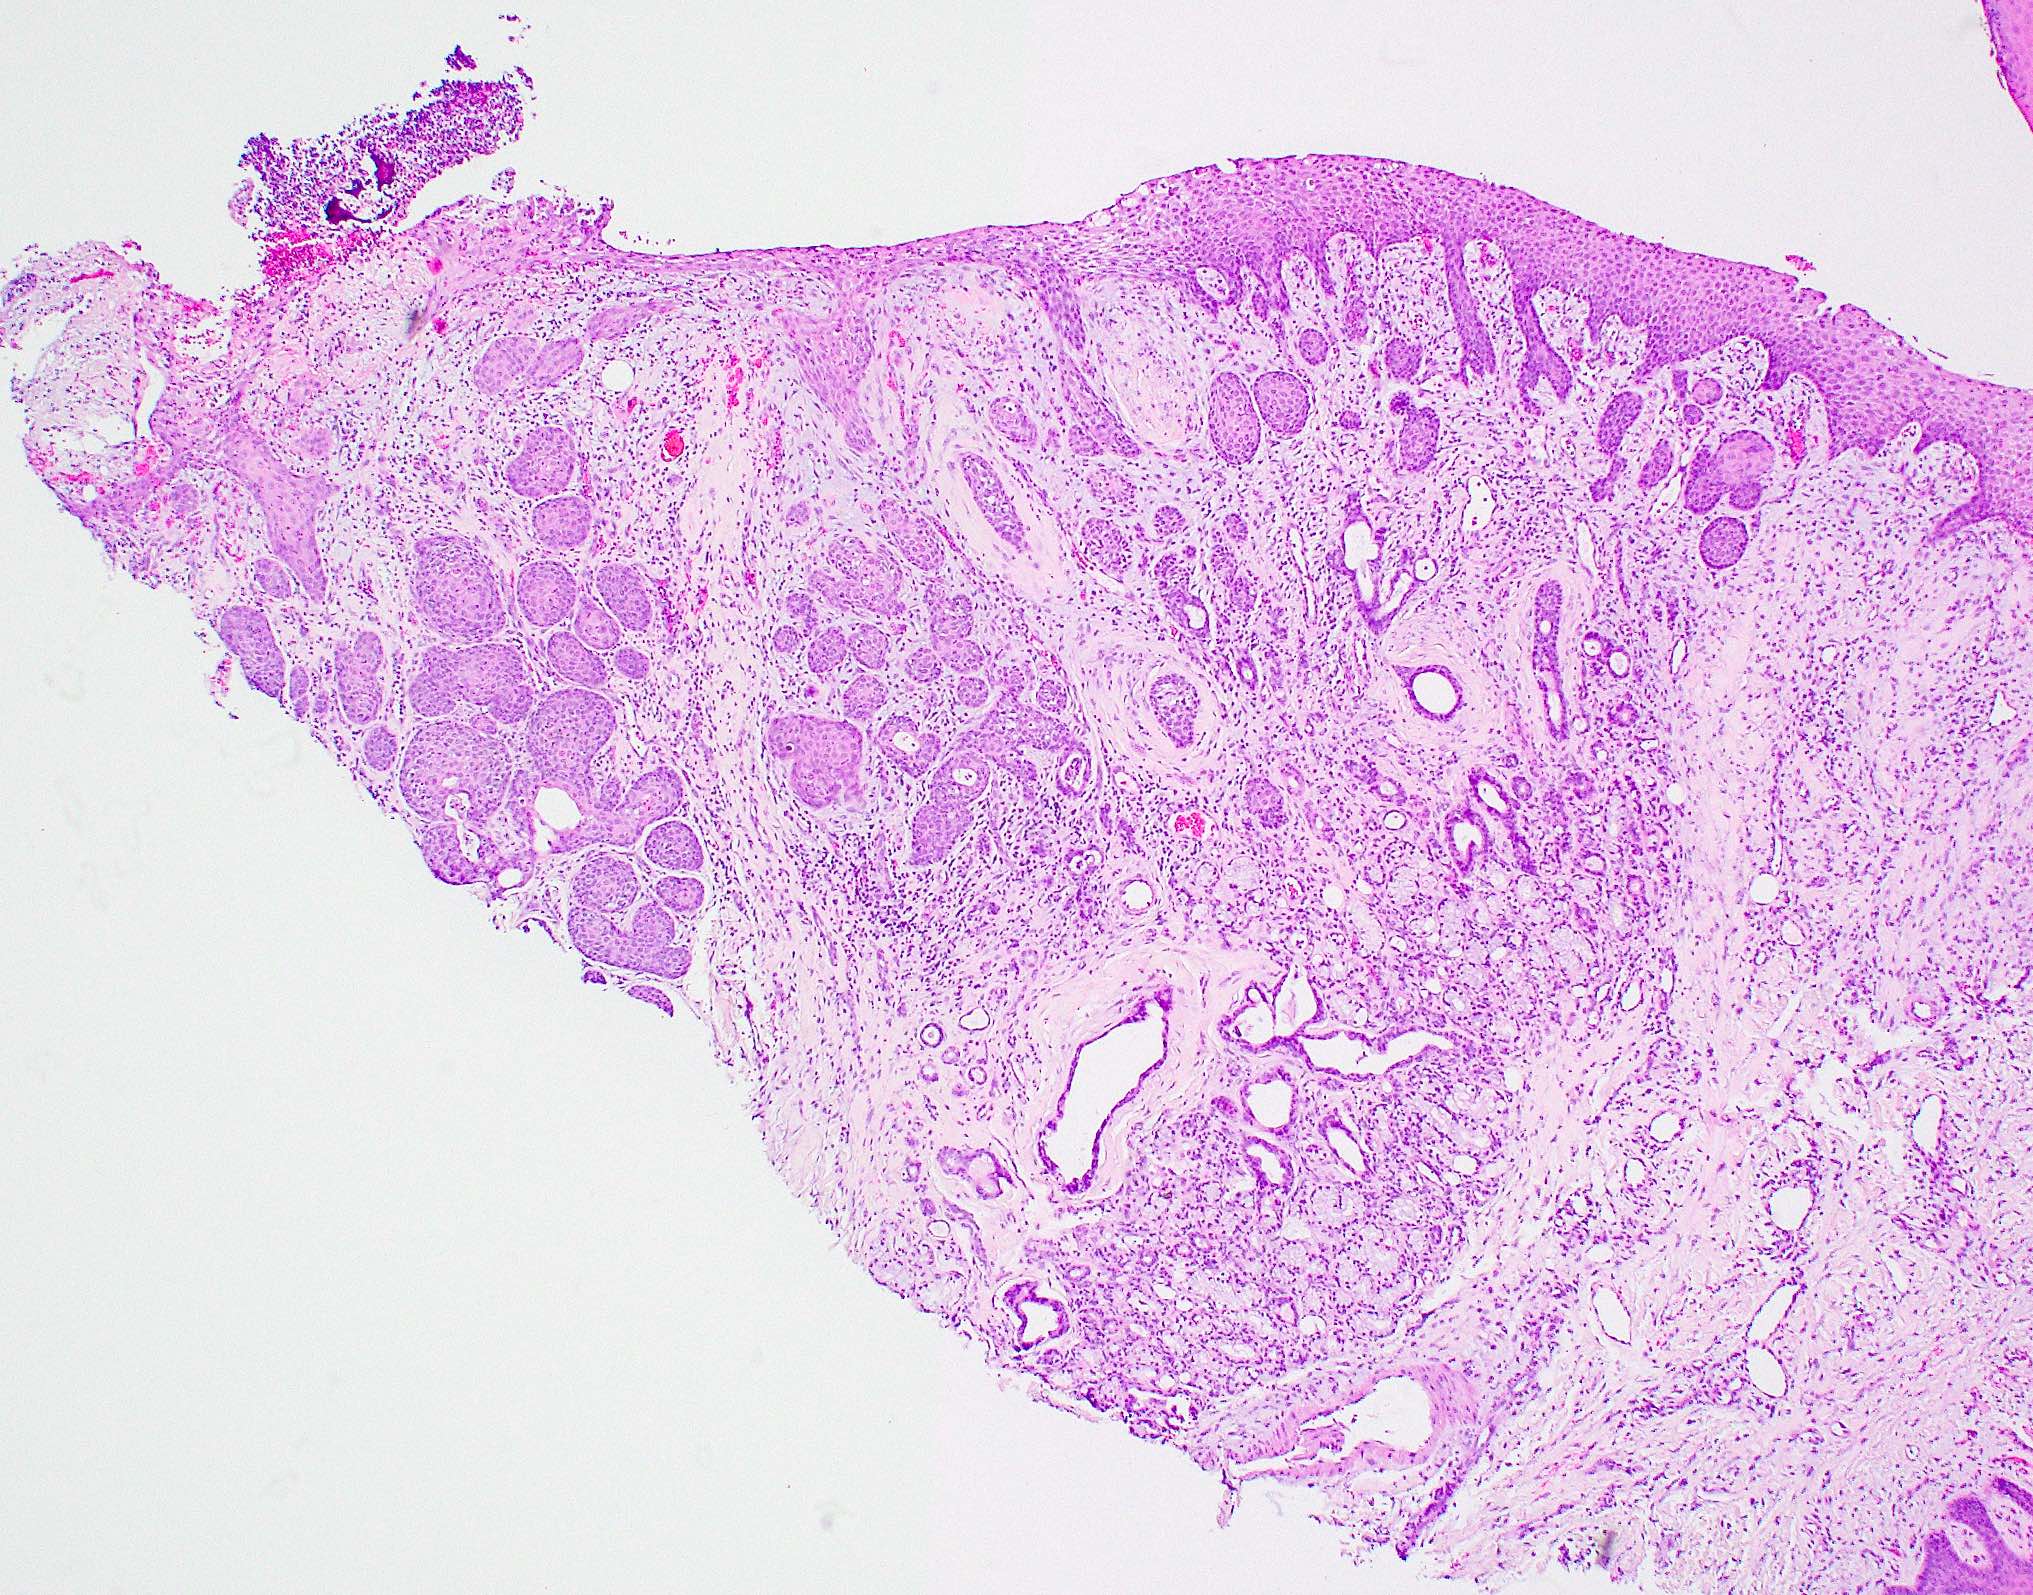

Microscopic (histologic) description

- Squamous metaplasia of ductal structures and acini with preservation of the salivary lobular architecture is an essential feature, according to World Health Organization (see WHO classification-oral cavity & oropharynx)

- Necrosis / infarction of acini characterized by loss of nuclei and cell borders with or without zones of spilled mucin

- Pseudoepitheliomatous hyperplasia with generally bland cytology or keratinocytic regenerative atypia

- Reactive, myxocollagenous background stroma

- Surface ulceration, granulation tissue and subacute inflammation may be present

- Has been conceptualized by 5 histologic stages of development and evolution: infarction, sequestration, ulceration, repair and healing (Int J Oral Surg 1982;11:283)

Microscopic (histologic) images